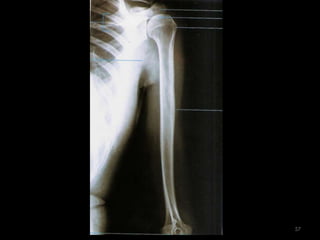

úmero51

Incidência AP Úmero52

53

54

Incidência lateral do úmero55